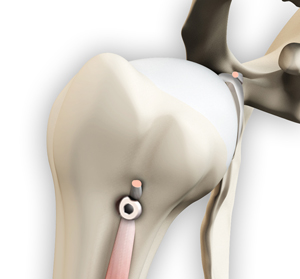

• Proximal Biceps Tenodesis

Proximal biceps tenodesis is the surgical reattachment of a torn proximal biceps tendon, which connects...